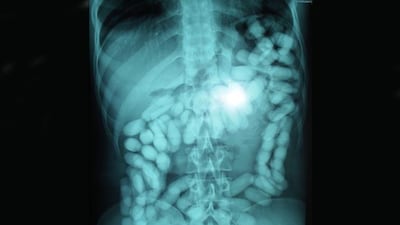

Many had dozens of latex-wrapped packages in their stomachs, typically swallowed with the help of olive oil.

"We referred suspects who carried as many as 100 capsules inside their stomachs for prosecution," said Saleh Al Shehhi of Dubai Narcotics Department.